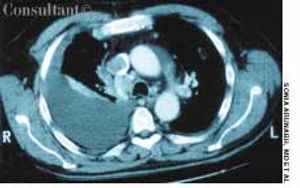

A 64-year-old woman with a history of diabetes, hypertension, and lymphoma was admitted to the hospital with a dull headache, conjunctival congestion, and slight dyspnea. Her pulse rate was 96 beats per minute; blood pressure, 146/68 mm Hg; and respiration rate, 22 breaths per minute. She also had increased jugular venous distention; cardiovascular and chest examination findings were normal. Edema of both arms and dilated blood vessels on the anterior chest wall were noted.